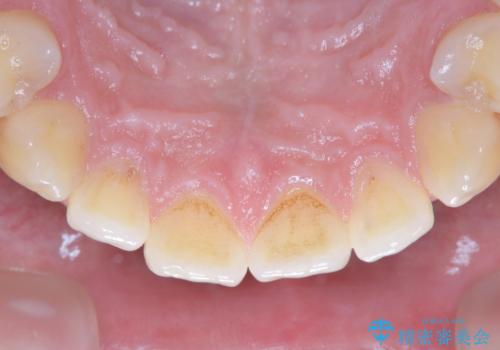

- 数年ぶりに歯科へ来院とのこと。全体的に歯のクリーニングをしてほしいとのことでした。

PMTC60分コースを行いました。

お口のトラブルを予防するには、PMTC(歯科医院で専門的な機械や材料を使用してクリーニング)を定期的に行うことが効果的な治療法です。

- 歯を白くする目的の施術ではありません